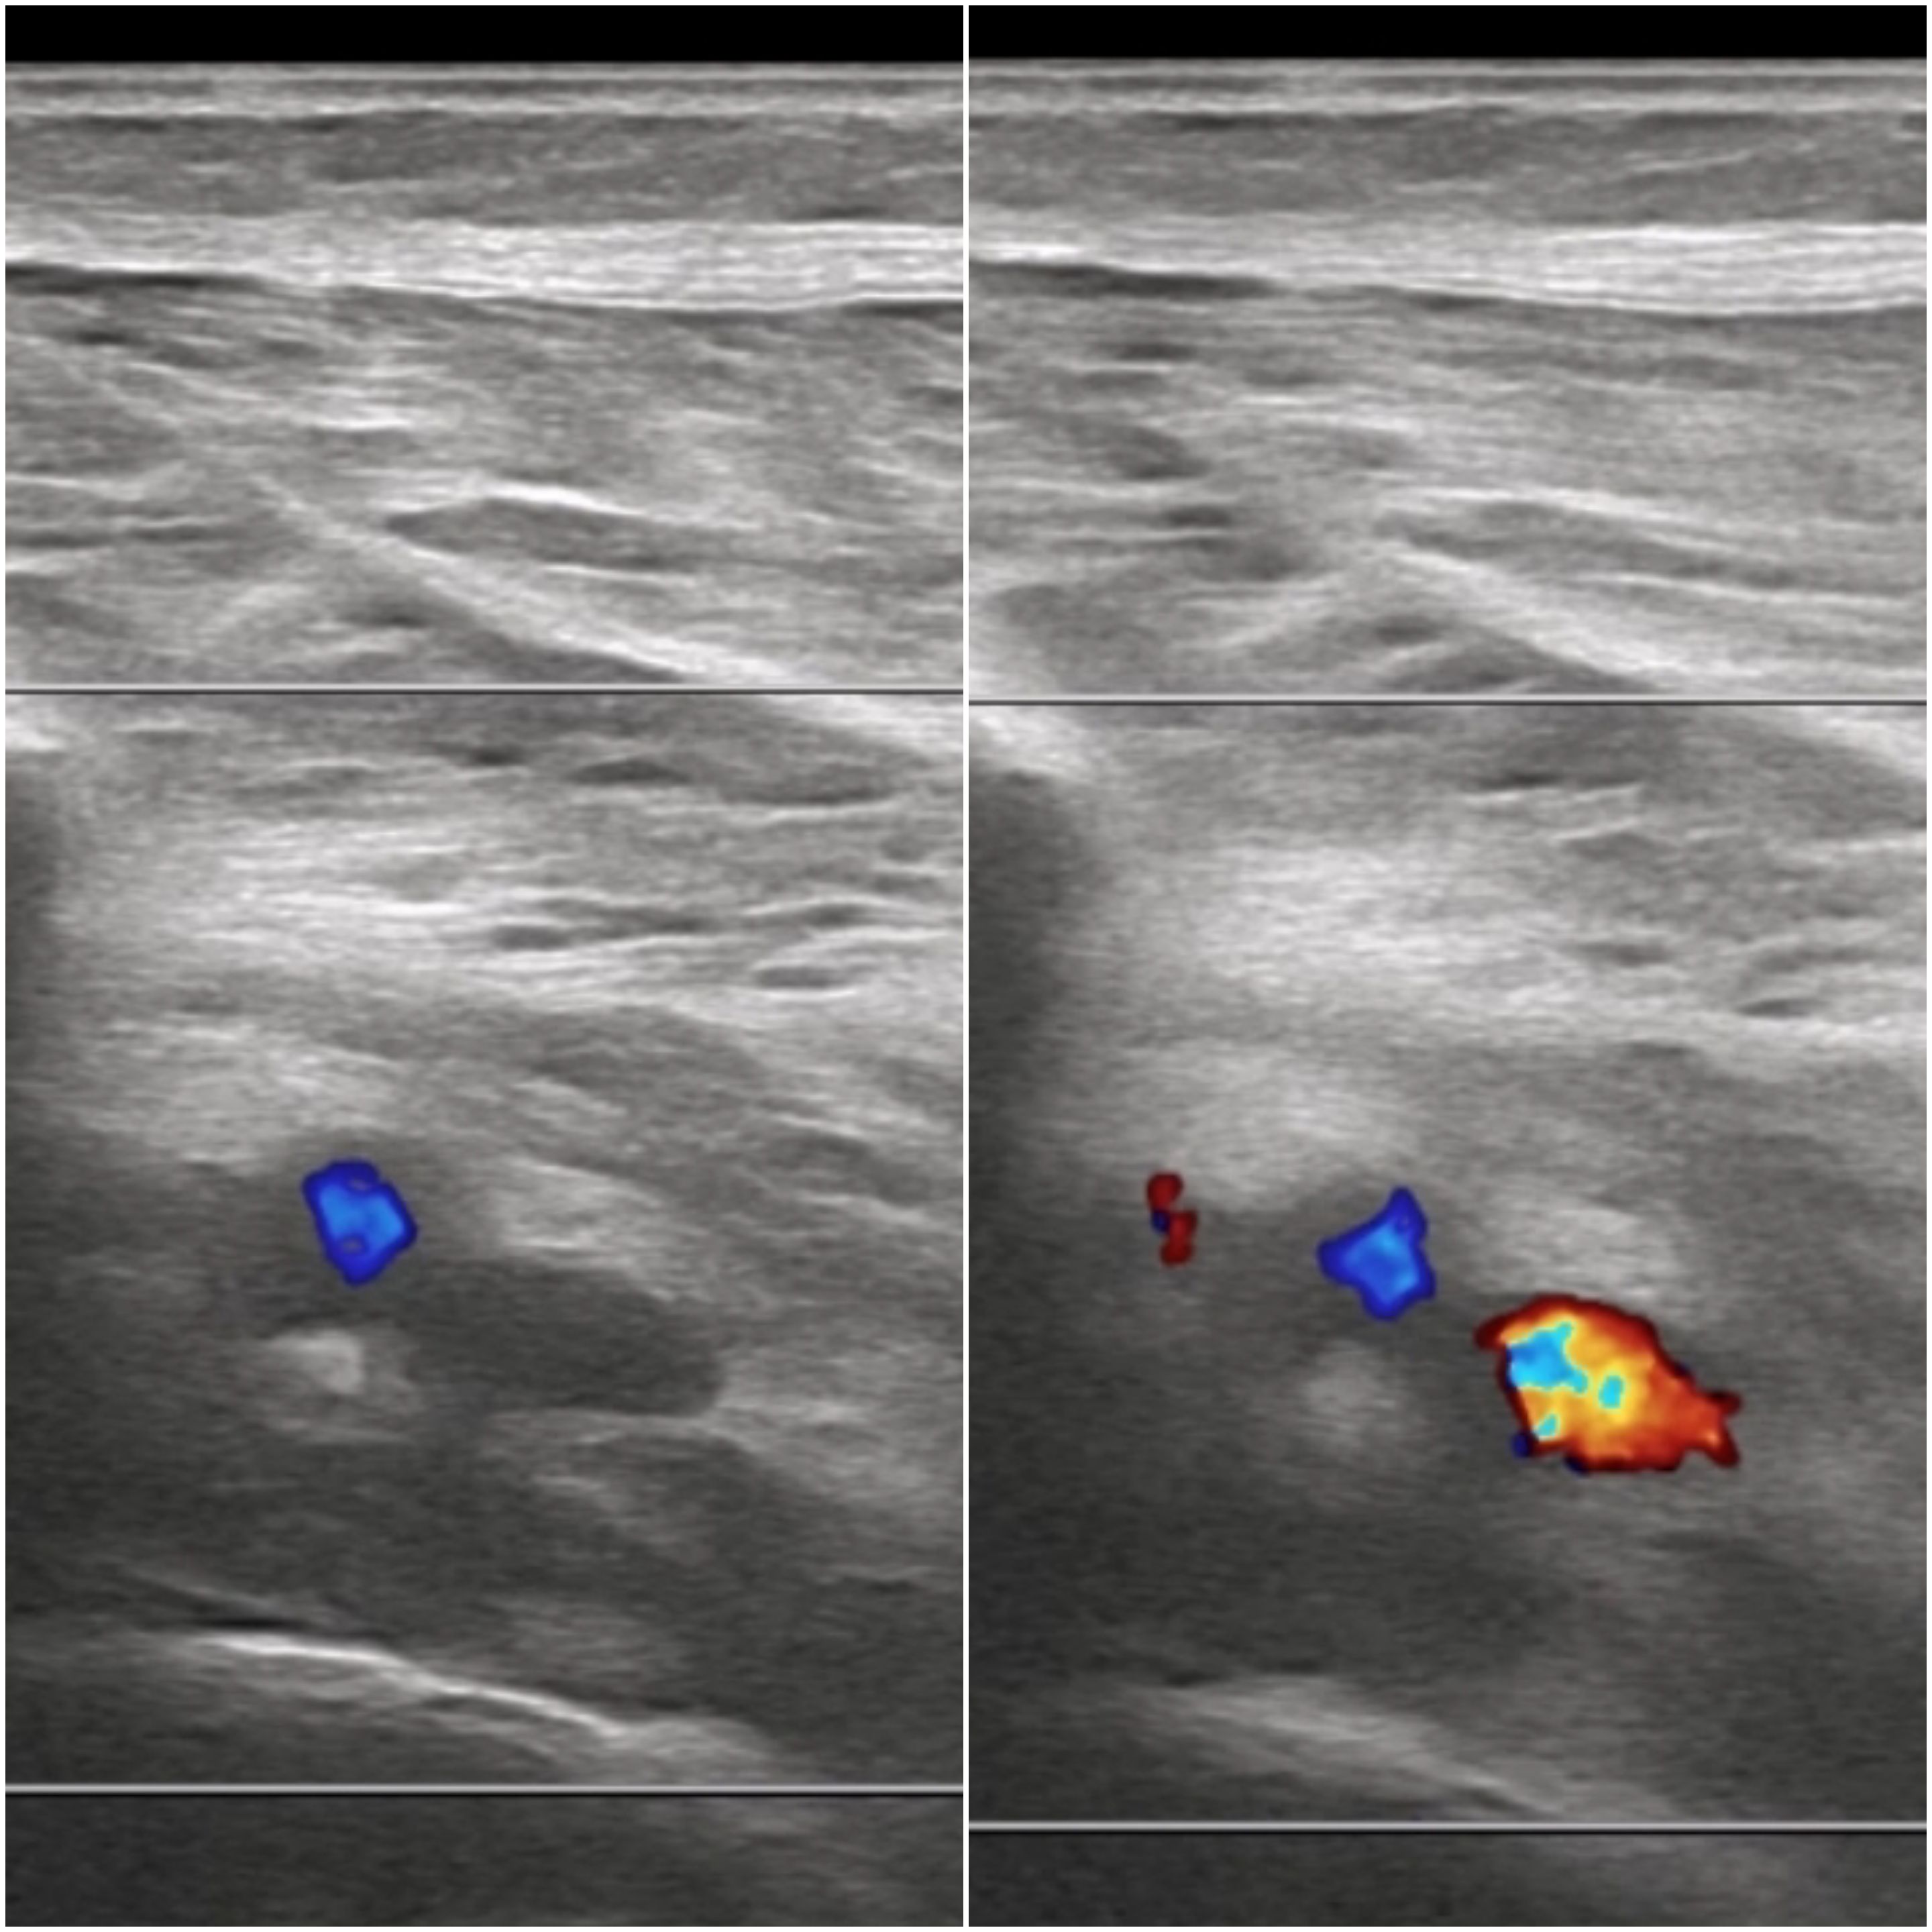

Ecografía clínica: no compresibilidad venosa, con signo de «oleada» negativo en venas tibiales posteriores.

Debemos conocer los signos ecográficos de la trombosis venosa: ausencia de flujo venoso, no compresibilidad, «oleada» negativo, material ecogénico intraluminal según la fase en la que esté y sin captación Doppler pulsado. En caso de tromboflebitis la localización será superficial. La rotura de fibras con clínica de dolor súbito como «una pedrada». La rotura de un quiste de Baker en cara posterior de la rodilla.